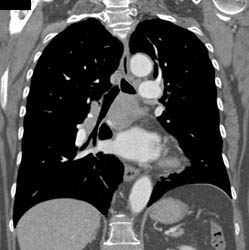

Patchy Nodule on Right Upper Lung